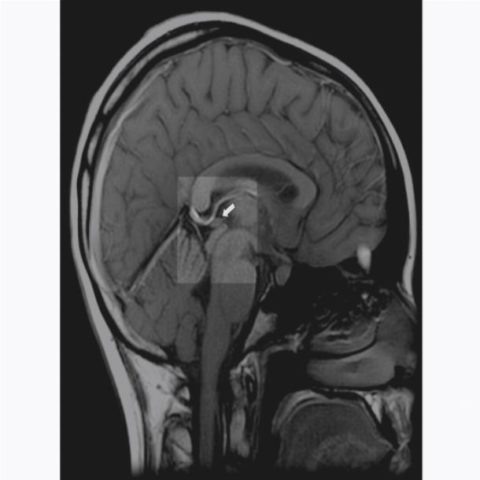

Киста сосудистого сплетения головного мозга у младенца

Под кистой понимают образование доброкачественного характера, которое имеет круглую форму, внутри заполнено жидкостью и окружено капсулой глиальной или эпителиальной ткани. В подавляющем большинстве случаев оно маленьких размеров и не имеет отрицательного воздействия на деятельность и функционирование мозга, поэтому формирование считается неопасным.

Чаще всего новообразование образуется в просвете сосудистого сплетения. Если обнаруживается в период между 14 и 22 неделей развития плода, то это считается одним из вариантов допустимой нормы, потому что обычно самостоятельно исчезает к моменту рождения ребенка.